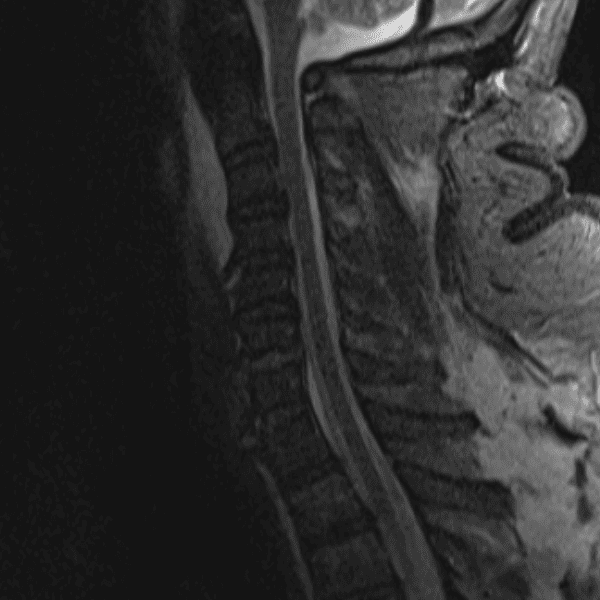

Simulates call by including subtle or difficult cases and some normals.

35 cases